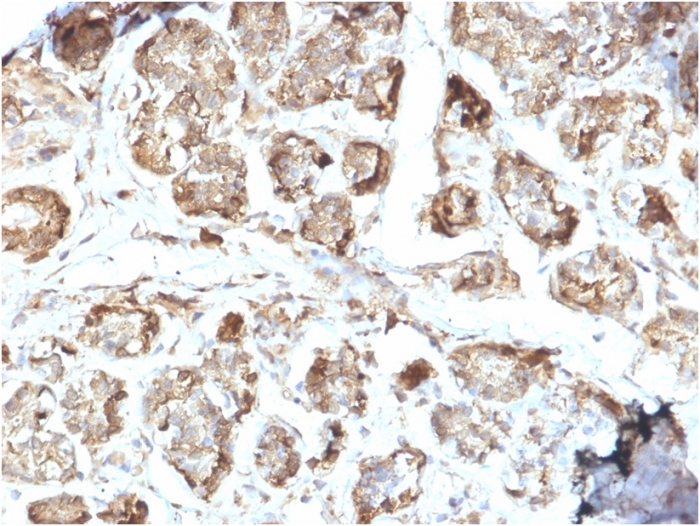

Immunohistochemistry (Formalin/PFA-fixed paraffin-embedded sections) - Anti-NME2 antibody [EPR8351] (AB131329)

• IHC-P

Immunohistochemistry (Formalin/PFA-fixed paraffin-embedded sections) analysis of human cerebrum tissue sections labeling NME2 with purified ab131329 at 1/500 dilution (0.22 µg/mL). Heat mediated antigen retrieval using Bond™ Epitope Retrieval Solution 2 (pH 9.0) . Rabbit specific IHC polymer detection kit HRP/DAB (ab209101) was used as the secondary antibody. Negative control : PBS instead of the primary antibody. Hematoxylin was used as a counterstain.